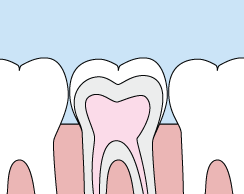

Crowns

Crowns are a cosmetic restoration used to improve your tooth's shape or to strengthen a tooth. Crowns are most often used for teeth that are broken, worn, or have portions destroyed by tooth decay.

Crowns are "caps" cemented onto an existing tooth which fully cover the portion of your tooth above the gum line. In effect, the crown becomes your tooth's new outer surface. Crowns can be made of porcelain, metal, or both. Porcelain crowns are most often preferred because they mimic the translucency of natural teeth and are very strong.

Crowns are often preferable to silver amalgam fillings. Unlike fillings which apply metal directly into your mouth, a crown is fabricated away from your mouth. Your crown is created in a lab from your unique tooth impression which allows a dental laboratory technician to examine all aspects of your bite and jaw movements. Your crown is then sculpted just for you so that your bite and jaw movements function normally once the crown is placed.